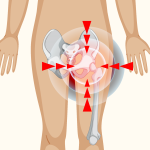

Understanding Frozen Shoulder: What It Is and How to Treat It Understanding Hip Osteoporosis: What You Need to Know

Understanding Hip Osteoporosis: What You Need to Know Tennis Elbow: Causes, Symptoms, and Physiotherapy Treatment Options